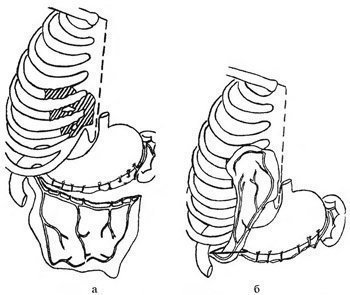

Şəkil

Kliniki müayinə zamanı döş qəfəsi divarında yumşaq konsistensiyalı, tənəffüs aktı zamanı ölçüsünü dəyişən, ağrısız şişkinlik müəyyən olunur. Rentgenoloji müayinə zamanı diaqnozu təsdiqləmək olur. Şübhəli hallarda KT müayinəsi çox faydalıdır, defektin ölçüsünü müəyyən etməyə imkan verir.

Şəkil

Şəkil